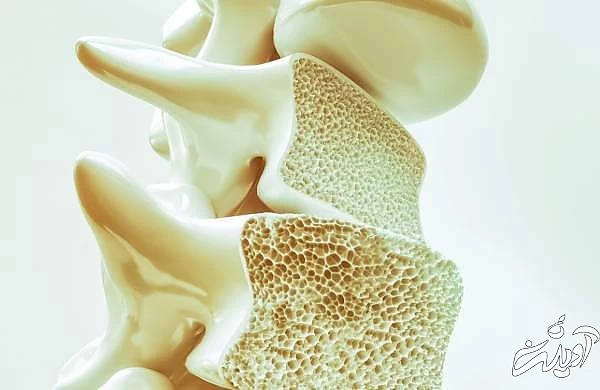

قبل از اطلاع از فواید چای لیمو، اجازه دهید تا بدانیم که چگونه چای لیمو را تهیه کنیم. این روش عمومی و پرکاربرد برای تهیه چای لیمو است. با تهیه آن به روش های مختلف می توانید چای لیمو را حتی خوشمزه تر کنید. انواع دیگر چای لیمو عبارتند از:چای یخی لیمو، چای سیاه لیمو و چای یخ زده آبلیمو و غیره. اگر می خواهید بدانید که چای لیمو برای چه چیزی مفید است ، پس باید به فواید سلامتی چای لیمو در متن ارائه شده در این بخش از بهداشت و سلامت توجه کنید. نوشیدن یک فنجان چای لیمو هر روز صبح به جای یک چای معمولی، تولید اسید معده را افزایش می دهد و باعث جذب مواد غذایی تجزیه شده می شود و مواد زائد یا سموم را از بین می برد. همچنین با هضم سالم غذا به بدن کمک می کند تا مواد مغذی اساسی را از مواد غذایی جذب کرده و سنگ کلیه را حل کند. اسیدیته چای لیمو علائم ناشی از سوزش قلب، نفخ و سوء هاضمه را کاهش می دهد. ویتامین C یکی از ویتامین های ضروری برای سنتز کلاژن و سیستم ایمنی سالم است. از آنجا که بدن به تنهایی نمی تواند ویتامین C را تولید کند، لازم است که ما مقدار کافی ویتامین C را از طریق یک رژیم غذایی سالم دریافت کنیم. برای تقویت سطح ویتامین C در بدن، باید روزانه 75 تا 90 میلی گرم آب لیمو مصرف کنید. چای لیمو پاک کننده و سم زدای خوبی است و با از بین بردن سموم از دستگاه گوارش بدن را پاکسازی می کند. این ماده ضد عفونی کننده عالی است و از بروز انواع مختلف عفونت ها و بیماری هایی که به بدن حمله می کنند جلوگیری می کند. این چای باعث می شود احساس انرژی بیشتر و بی حالی کمتر کنید. چای لیمو همچنین در تقویت آرامش مفید است و به خستگی کمک می کند. بسیاری از افراد می دانند که نوشیدن آب لیمو به کاهش وزن بدن کمک می کند با این حال، چای لیمو ترش بیشتر مفید است زیرا هر روز صبح آن را به صورت گرم می نوشیم. بسیاری از افراد نوشیدن این چای معجزه آسا را آغاز کرده اند زیرا باعث می شود بدن 3 برابر سریع تر، کمبودهای جریان خون را جذب کند. این چای باعث از بین رفتن چربی شکم می شود ؛ اسید سیتریک موجود در لیمو باعث کاهش جذب قند توسط بدن می شود ، زیرا این قندها به چربی تبدیل می شوند. چای لیمو علاوه بر تقویت سوخت و ساز بدن ، سطح pH بدن را نیز متعادل می کند، همچنین بدن را هیدراته نگه می دارد که به کاهش وزن کمک می کند به این ترتیب چای لیمو برای کاهش وزن مفید است. نوشیدن چای لیمو با اضافه کردن زنجبیل به آن به صورت 3 تا 4 بار در روز به کاهش سرماخوردگی و آنفولانزا کمک می کند. این چای همچنین باعث تسکین گلودرد و تقویت سیستم ایمنی بدن می شود. چای لیمو می تواند به مخاط گلو کمک کند و شما را گرم نگه می دارد. نوشیدن چای می تواند با جذب آهن توسط بدن ارتباط داشته باشد. اما وقتی نوبت به چای لیمو می رسد، ویتامین C موجود در آن به تقویت جذب آهن غیرهمی توسط بدن کمک خواهد کرد بنابراین، با مصرف مرتب چای لیمو، این مزایا را دریافت کنید. ترکیبی به نام هسپریدین در لیمو موجود است که می تواند عملکرد آنزیم ها را تغییر دهد. این امر در کنترل سطح قند خون در بدن مفید است. اگر عادت به نوشیدن روزانه چای لیمو داشته باشید، می توانید از این مزایا استفاده کنید. چای لیمو سموم خون را از بدن خارج می کند و از این رو انرژی بدن شما را تقویت می کند، همچنین باعث تازه و راحت شدن ذهن می شود . استرس مسئول تولید سموم در خون است که باعث ایجاد مشکلات مختلف سلامت روان می شود. چای لیمو یک درمان عالی برای سردرد، ضعف ، استرس ، نشاط کم، بی حالی و خستگی است. چای لیمو با پاکسازی خون، شما را سالم و سر حال نگه می دارد. مواد ادرار آور مثل چای لیمو ، تولید ادرار را افزایش می دهند، این موارد توسط پزشکان برای معالجه بیماری های مختلف مانند سنگ کلیه که به دلیل وجود آب زیاد در بدن، ادم، فشار خون بالا، پوکی استخوان و تخمدان های پلی کیستیک تشکیل شده است، تجویز می شوند. کلیه برای دفع آب بیشتر است و به خلاص شدن از شر آن همه مشکلات سلامتی کمک می کند. چای لیمو یکی از انواع چای است که دارای فلاونوئیدها می باشد و التهاب و چربی ها را کاهش می دهد. این چای می تواند مانع از تشکیل لخته های خون در عروق شود. بنابراین، چای لیمو به محافظت از مشکلات قلبی کمک می کند. دو تا سه فنجان چای لیمو در روز با زنجبیل اضافه شده در آن به شما کمک می کند که از خاصیت ضد عفونی کننده این چای استفاده کنید. خواصی مانند آنتی ویروسی و ضد باکتریایی که در لیمو وجود دارد، به درمان بیماری ها و عفونت های درمانی کمک می کند بنابراین، برای دریافت فواید این چای لیمو، روزانه این چای را مصرف کنید. ویتامین C موجود در لیمو برای پوست بسیار مفید است. در مبارزه با جوش ها و آکنه ،پاک کردن لکه های تیره، روشن کردن رنگ پوست و شفافیت پوست کمک می کند. آنتی اکسیدان های موجود در لیمو از ایجاد چین و چروک جلوگیری می کنند پس با نوشیدن چای لیمو به طور منظم می توانید پوست خود را سالم و درخشان جلوه دهید. آنتی اکسیدان های موجود در چای لیمو به مبارزه با رادیکال های آزاد کمک می کند و باعث تقویت ایمنی بدن می شود. آنتی اکسیدان ویتامین C ،استحکام دندان ها و استخوان ها را تقویت می کند ، همچنین از آسیب های ایجاد شده به سلول های سالم بدن جلوگیری می کند. لیمو با تحریک سلول های ناسالم و تخریب شده از رشد سرطان یا سلول های سرطانی در بدن جلوگیری می کند. با نوشیدن چای لیمو می توان احتمال ابتلا به سرطان پوست، سرطان سینه و تعداد کمی از سرطان های دیگر را کاهش داد ، زیرا این ماده خواص ضد سرطانی دارد. تورم یا ورم جراحی یک مشکل شایع بعد از عمل های جراحی است که در اثر تزریق سلول های مرده چربی و خون آبه در کنار هم ایجاد می شود، مایعات با جمع شدن بین بافت های بدن باعث ایجاد درد و ناراحتی می شوند. چای لیمو اغلب برای کاهش و بهبود شرایط تورم توسط پزشکان توصیه می شود. علاوه بر آن چای لیمو اثرات سمی بیهوشی را از بین می برد و باعث کاهش درد در چرخه قاعدگی زنان می شود این چای همچنین در کاهش سردرد، نشاط کم، خستگی و افسردگی و سایر موارد اختلالات نیز کمک می کند. چنانچه در بخش سلامت اشاره کرده ایم نوشیدن چای لیمو با احتیاط های خاص به افراد کمک می کند تا تمام مزایای آن را بدست آورند. با این حال، برای افراد در سنین مختلف و افرادی که مشکلات بهداشتی زیر را دارند مناسب نیست. از آنجا که آب لیمو جزو مرکبات است، می تواند برای ایجاد حساسیت و آسیب پذیری دندان ها مضر باشد. برای جلوگیری از این امر، همیشه بعد از نوشیدن این چای، آب غرغره کنید. چای لیمو در دوران بارداری بی خطر نیست زیرا حاوی کافئین است. قطعا هر چقدر که سنتان بالاتر می رود، تمایل ندارید که به زخم معده یا پوکی استخوان دچار شوید؛ خوب ، اگر هر روز بیش از اندازه چای لیمو بخورید به این بیماری ها در سنین بالا مبتلا خواهید شد .چای لیمو در کنار تمام خواصی که دارد در صورت مصرف بیش از حد عوارضی به وجود می آورد که برای بدن مضر است و در اینجا برخی از عوارض جانبی جدی چای لیمو را بررسی می کنیم. افرادی که چای لیمو را به طور مرتب مصرف می کنند شاهد علائم پوسیدگی در مینای دندان هستند. چای لیمو می تواند یک قاتل خاموش برای مینای دندان شما باشد و دندان های شما را مستعد درد حاد و حساس به تغییرات شدید دما می کند. مصرف بیش از حد چای لیمو می تواند سطح pH معده و روده شما را تغییر داده و باعث ایجاد ریفلاکس اسیدی در جایی که اسید معده به مری منتقل می شود، گردد. این تغییرات باعث احساس سوزش در قفسه سینه و گاهی استفراغ می شود. همانطور که گفته شد لیمو خاصیت ادرارآور دارد، در صورت مصرف زیاد با فشار مکرر برای دفع ادرار، باعث کم آبی بدن در بدن می شود. نوشیدن زیاد چای لیمو باعث تحریک غشاهای مخاطی می شود و به ممکن است منجر به زخم های دهان و لثه شود. چای لیمو می تواند در دهان شما نقش مخربی را ایفا کند. به خانم های باردار توصیه می شود که از مصرف چای لیموترش خودداری کنند زیرا حاوی کافئین است. مصرف زیاد چای لیمو خطر سقط جنین یا سایر عوارض جانبی شدید را افزایش می دهد. زنانی که به نوزاد خود شیر می دهند نیز باید از چای لیمو دوری کنند. بله، چای لیمو سرشار از طراوت است - دقیقاً همان چیزی که یک مادر خسته نیاز دارد. اما کافئین موجود در چای با شیر مادر مخلوط می شود و می تواند به کودکی که تنها از شیر ادر تغذیه می کند آسیب برساند. وقتی لیمو را به چای خود اضافه می کنید، آلومینیوم موجود در چای در بدن جذب می شود، این اتفاق با نوشیدن چای معمولی رخ نمی دهد . آلومینیوم جذب شده باعث ایجاد مسمومیت در بدن می شود، که می تواند منجر به آنسفالوپاتی، استئوماسیا یا بیماری استخوانی اپلستیک، میوپاتی پروگزیمال، افزایش خطر عفونت، افزایش توده بطن چپ و کاهش عملکرد میوکارد و آنمی میکروسیتیک با سطح بسیار بالا و حتی مرگ ناگهانی شود. چای لیمو بی سر و صدا مقدار زیادی کلسیم را از طریق ادرار از بدن خارج می کند که باعث پوکی استخوان در سنین بالا شود. مطالعات میزان مصرف چای لیمو را با احتمال ابتلا به بیماری آلزایمر در مراحل بعدی زندگی مرتبط دانسته اند. مصرف منظم چای لیمو می تواند باعث تجمع پلاک در مغز شود که با شروع آلزایمر ارتباط دارد. در برخی افراد، مصرف منظم چای لیمو می تواند باعث درد معده، اسهال، سندرم روده تحریک پذیر و حتی زخم شود. همه این عوارض جانبی چای لیمو جدی است، اما به این معنی نیست که خودتان را کاملاً از منبع آرامش بخش روزانه این چای محروم کنید. تنها کاری که باید انجام دهید مصرف آن را متعادل کنید. بیش از یک فنجان در روز ننوشید و در صورت امکان، صبح هنگام خالی بودن معده از خوردن آن از صبحانه خودداری کنید. اگر علائمی مانند حساسیت دندان، درد معده یا حالت تهوع را احساس کردید، مصرف این چای را متوقف کنید و با پزشک خود مشورت کنید و در مورد فواید چای لیمو و عوارض جانبی آن مشاوره بگیرید. ک

پوکی استخوان